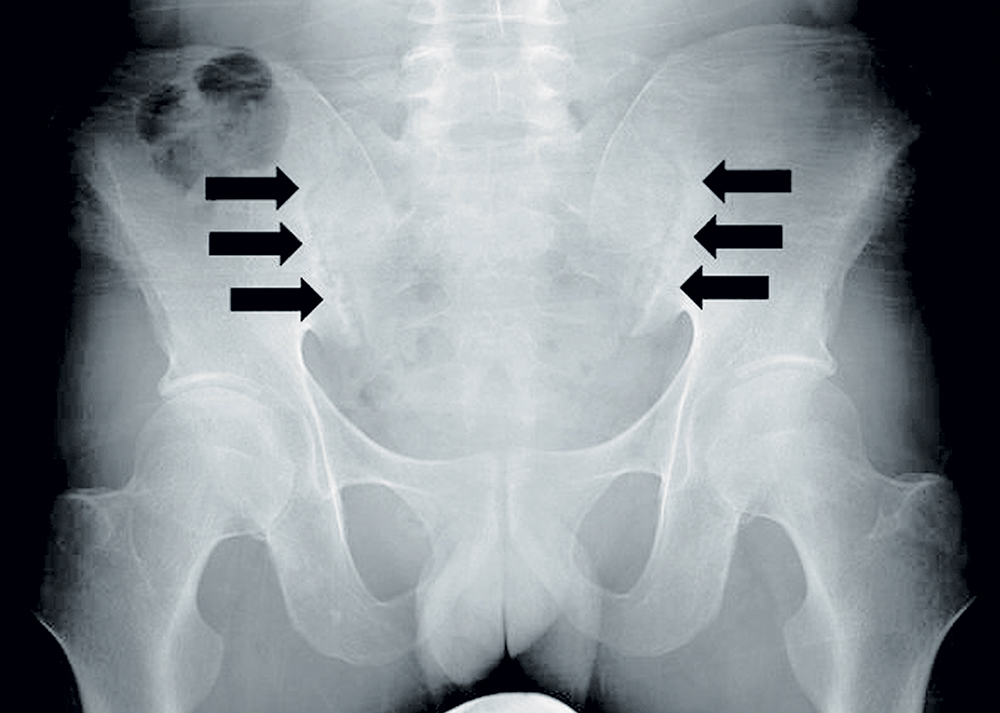

Lazimnya sakit belakang yang sering dialami oleh golongan muda adalah akibat daripada kekejangan otot atau ligamen tulang belakang dikenali sebagai lower back strain. Berlaku secara tiba-tiba disebabkan oleh aktiviti yang membebankan di bahagian belakang tubuh dan mengambil masa beberapa minggu untuk pulih. Namun sekiranya sakit belakang ini berterusan dan tiada kaitan dengan aktiviti lasak, kerap berlaku pada waktu malam atau pagi, pergerakan tulang belakang yang terhad, sentiasa letih atau terdapat…